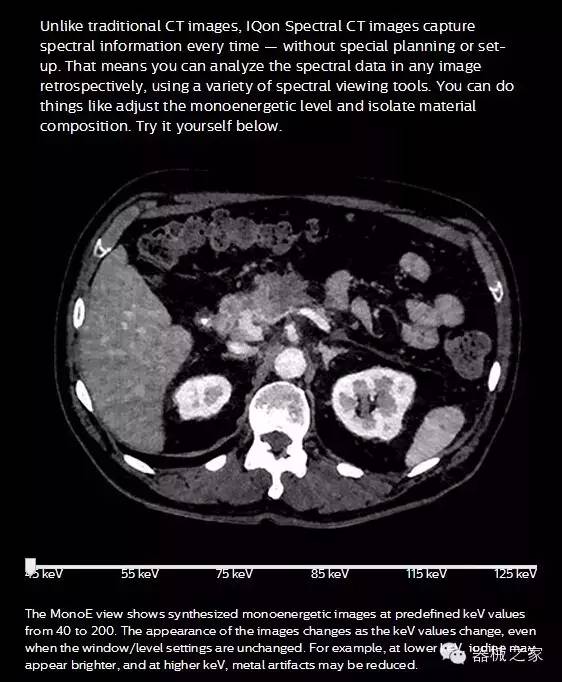

IQon光譜CT能夠按照需求提供光譜量化和工具,并能通過(guò)簡(jiǎn)單工作流程、在低劑量下對結構進(jìn)行定性分析

IQon光譜CT -- 是業(yè)界首臺以探測器為成像基礎的光譜CT,它可以在單次常規掃描下獲得傳統解剖影像及光譜功能影像。不僅可以提供精準的診斷信息,還可簡(jiǎn)化工作流程、在低劑量下完成定量與定性分析。